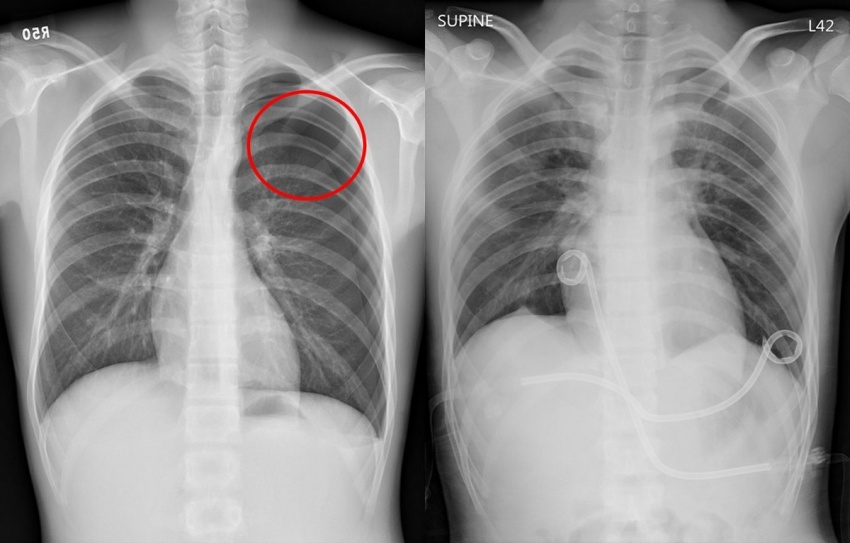

▲鄭同學因氣胸導致肺部塌陷(圖左紅圈處),經劍突下單孔胸腔內視鏡雙側肺泡切除術併肋膜沾黏術後肺部完全擴張(右)。

台北慈濟醫院胸腔外科醫師洪嘉聰表示,這位鄭同學急診送來的時候,發現他是自發性氣胸復發。因為他右側胸也曾發作過,因為只要發作過1次,復發率是30%到50%,再次發生後,復發率升高到5成到7成。考量鄭同學發作次數頻繁,洪嘉聰「劍突下單孔胸腔內視鏡雙側肺泡切除術併肋膜沾黏術」為他治療,術後第5天,他便平安出院,免於氣胸復發之苦。

洪嘉聰表示,氣胸是指因外傷或在無任何外在因素的情況下,發生肺泡破裂,導致空氣不正常進入肋膜腔,引發肺臟部分或完全塌陷,使患者出現胸痛或呼吸困難等症狀。前者是外傷性,後者稱為「自發性氣胸」。